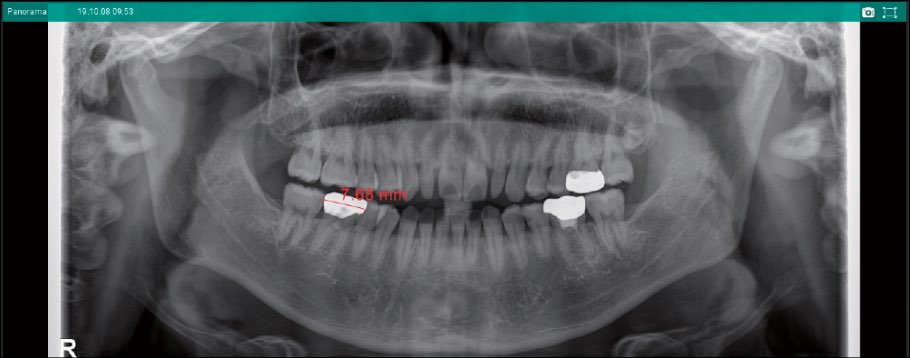

計測ツール

距離計測、角度計測、ラインプロファイルなど、便利な計測ツールを用意しています。